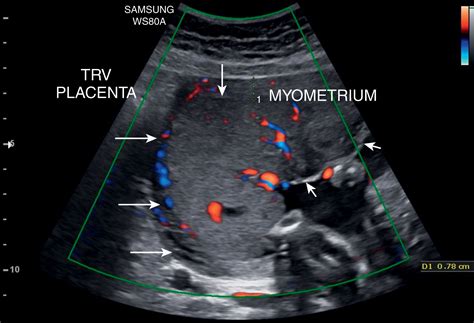

The placenta is a temporary organ that develops in the uterus during pregnancy. It serves as a lifeline between the mother and the fetus, facilitating the exchange of nutrients, gases, and waste products. Lakes In The Placenta refer to small, fluid-filled spaces within the placental tissue. These lakes are not typically visible to the naked eye but can be detected through advanced imaging techniques and histological examinations.

• Ultrasound Imaging: High-resolution ultrasound can sometimes detect the presence of lakes, although this method is not always reliable.

• Magnetic Resonance Imaging (MRI): MRI provides detailed images of the placenta and can help identify lakes more accurately.

• placental lake on ultrasound